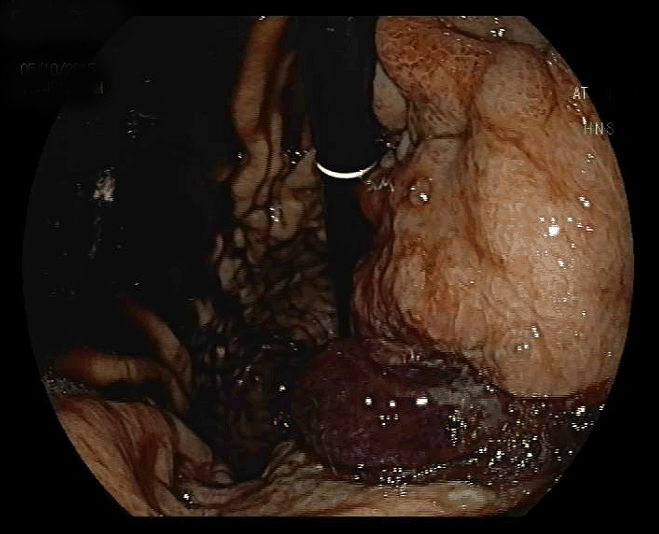

A 38-year-old male with a past medical history of Crohn’s disease, receiving mesalazine and azathioprine therapy for the last three years was admitted to the emergency room with melena. Gastroscopy revealed intact gastric mucosa and bleeding ulcerated advanced gastric cancer (AGC) (Figure 1). The signet ring cell gastric cancer was diagnosed by biopsy.

Figure 1: Lesion lies from posterior wall of corpus to antrum with slightly depressed and ulcerated base.